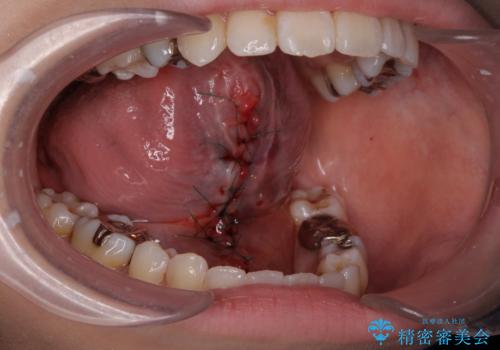

舌が動かしにくいから舌小帯を切りたい

- 舌が動かしにくく、過去に舌小帯切除を行ったがあまり切除されず後戻りをしたため、舌小帯切除を希望されました。

舌小帯の形成術を行い、舌の可動域を広げました。